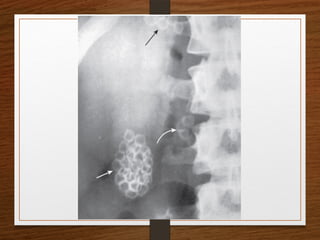

• C - C is for Calcification

 Look for clinically significant calcified structures such as

renal calculus, nephrocalcinosis, pancreatic calcification and

an abdominal aortic aneurysm (AAA), calcified gallstones

 Look for clinically insignificant calcified structures such as

costal cartilage calcification, phleboliths, mesenteric lymph

nodes, calcified fibroids, prostate calcification and vascular

calcification

What are the D/D of a radiopaque shadow in this region?

• Kidney stone

• Gallstones

• Pancreatic calculi

• Foreign body

• Fecolith

• Phleboliths

• calcified lymph node

• calcified renal tuberculosis

• calcified adrenal gland

• chip fracture of a transverse process of vertebra or calcification of costal

cartilage

What are theD/D of a radiopaque shadow in this region? • Kidney stone • Gallstones • Pancreatic calculi • Foreign body • Fecolith • Phleboliths • calcified lymph node • calcified renal tuberculosis • calcified adrenal gland • chip fracture of a transverse process of vertebra or calcification of costal cartilage